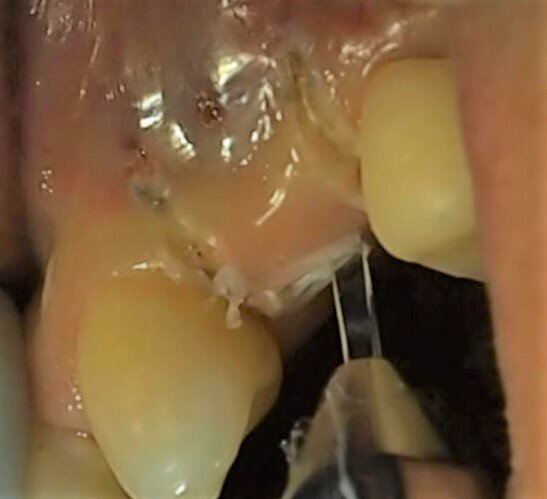

Fig. 9 - Caso clinico 2. Incisione dei tessuti molli: si apprezza il controllo dell’emostasi.